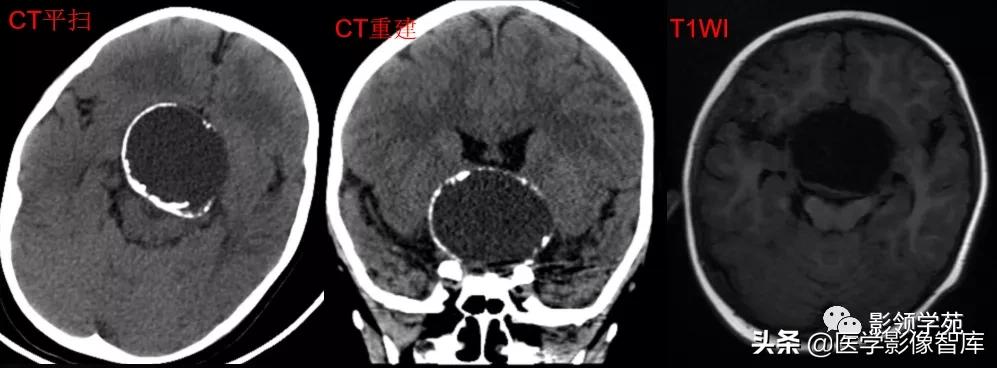

女 72岁,发现糖尿病3年余

鞍上区见一团块状稍高密度影,边界尚清,密度均匀。

鞍上右上方见一类椭圆形流空影。

病灶明显强化(瘤内血栓未强化),边界清楚,与右侧颈内动脉海绵段分界不清。垂体大小、形态未见异常。